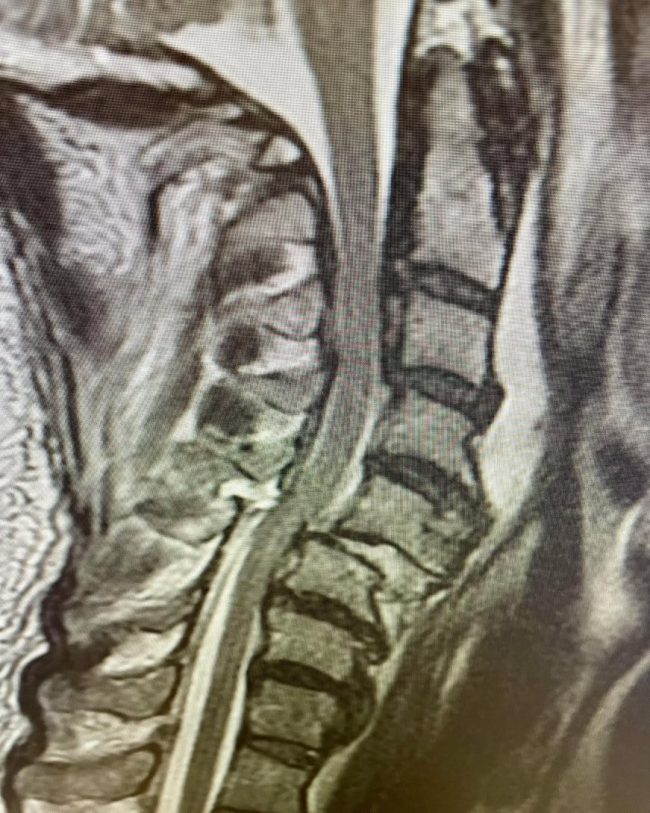

89-Year-Old with C5–6 Fracture-Dislocation: Surgical Stabilization

“Taking a call at a Level 1 trauma center is stressful and takes time away from family and a neurosurgeon’s precious free time. I was reminded recently why I still feel passionate about taking a Level 1 trauma call when I met this simply miraculous 89-year-old woman. She was involved in a motor vehicle collision…